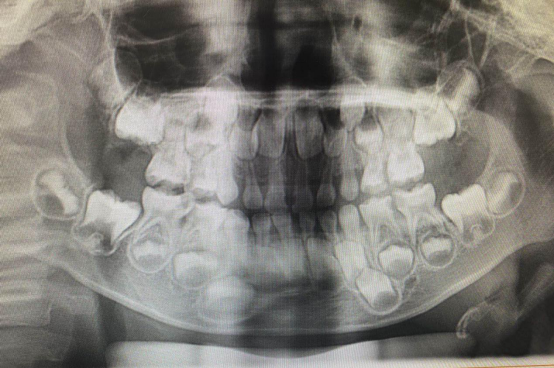

术前患儿X片检查结果

5岁的宋小朋友因右侧牙疼痛3天伴夜间疼痛加重来我院口腔科就诊,行面部曲面断层发现全口多颗牙龋坏,需行口内进一步检查,发现此时患儿已出现右面部肿胀及全身低热症状,经数位儿童口腔科医生评估,该患儿面部肿胀及低热是由牙齿引起,需尽快完成全口牙治疗。但是由于患儿哭闹不配合,无法在门诊正常行牙齿治疗,需要在全麻下进行综合治疗,与患者家属沟通后,患者家属知情并同意手术。术前排除了手术绝对禁忌症,儿牙全麻医疗团队根据曲面断层片及患儿临床症状,制定出最适合患者的治疗方案,手术过程顺利,共治疗16颗牙齿。术后患儿恢复很好,因牙疼痛而难过的脸上终于露出了开心的笑容。